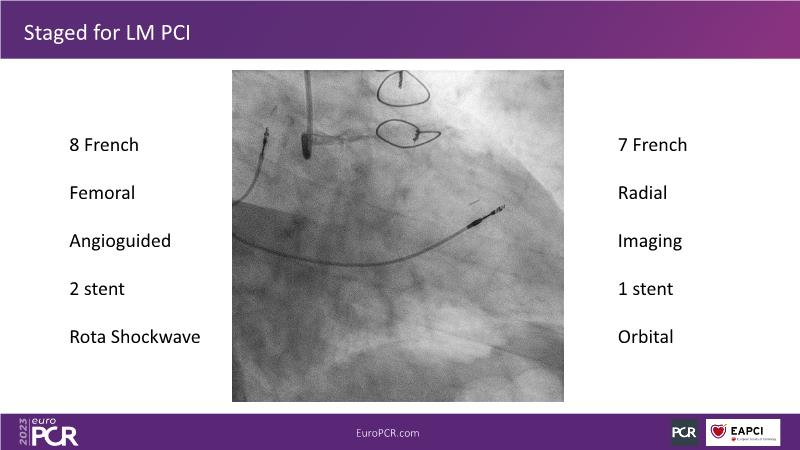

The aim of this session is to address the question of how to optimise outcomes for high-risk patients by analyzing two real-life cases for discussion: a distal calcified left main trifurcation and a high-risk PCI with orbital atherectomy.